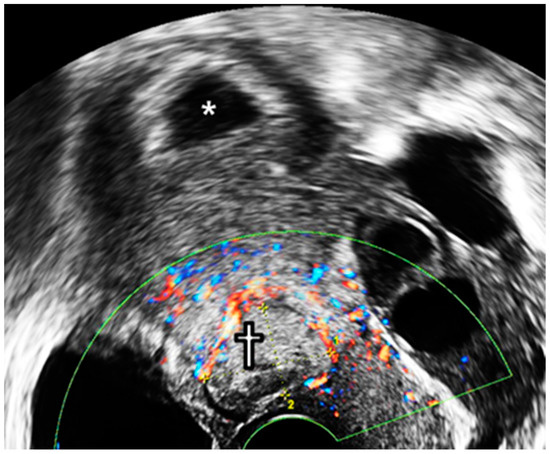

A sonographic examination at 10 GW revealed that the placenta around the reduction site had grown into the uterine cervix, resulting in intermittent vaginal spotting and a shortening of the cervical length. Considering a cervical length of less than 10 mm and the protrusion of the remnant placenta into the internal os (Figure 4a), a uterine cervical cerclage was inserted at 12 GW by placing the cervical intruding placenta inside the uterine cavity. The purpose of the cerclage was to control the growth of the remaining placenta in the CSP, as well as vaginal bleeding (Figure 4b,c). McDonald operation with double ligations using braided polyester thread (EthibondTM, Ethicon, New Jersey were implemented in the cervical cerclage [4]. A previous retrospective study reported that the braided thread suture in the cervical cerclage showed an improvement in neonatal survival, the prevention of preterm birth before 28 GW, less PPROM, and maternal febrile morbidity, compared to Mersilene tape (Mersilene™, Ethicon, Somerville, NJ, USA). [5]. Ultrasonography at 24+3 GW showed dilated and tortuous blood vessels encompassing the lesion (10 × 6 × 3 cm3 in volume), suggestive of an enlarged arteriovenous malformation (AVM) (Figure 4d). During the antenatal period, there were no severe complications, including preterm labor and short cervical length.

Figure 4. Management of arterio-venous malformation after selective CSP embryo reduction. (a) Ultrasonography to visualize RGT with cervical shortening at 10+3 GW before cervical cerclage. The RGT went into the uterine cervical internal os. (b) Transvaginal ultrasonography at 12+3 GW after the cerclage. (c) Effect of cervical cerclage role on HCSP management (details are written in the discussion section). (d) Ultrasound examination at 24+3 GW. Enlarged arterio-venous circulation was observed in the demised CSP (†); asterisk (*) indicates the fetal foot. CSP—cesarean scar pregnancy; GW—gestational weeks; RGT—remnant gestational tissue.